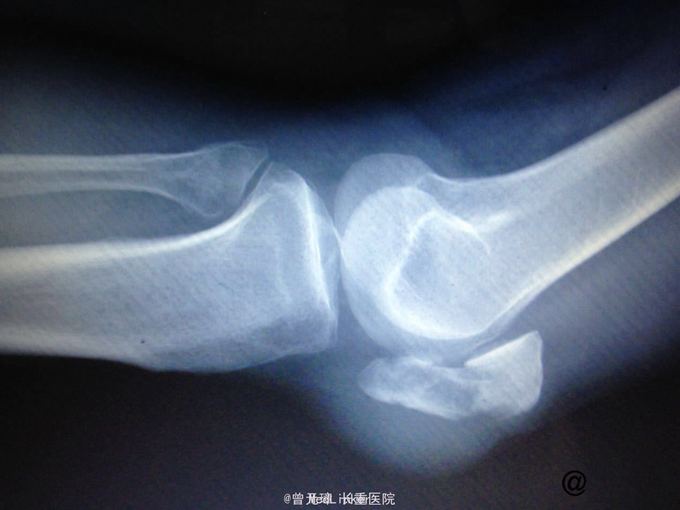

正常髌骨x片,正常跟骨x片

主诉 病史 外伤后左膝疼痛不适,屈伸不能.x片示左髌骨骨折

髌骨骨折片子图片

髌骨骨裂x光图片

髌骨骨折x线图片

髌骨骨折